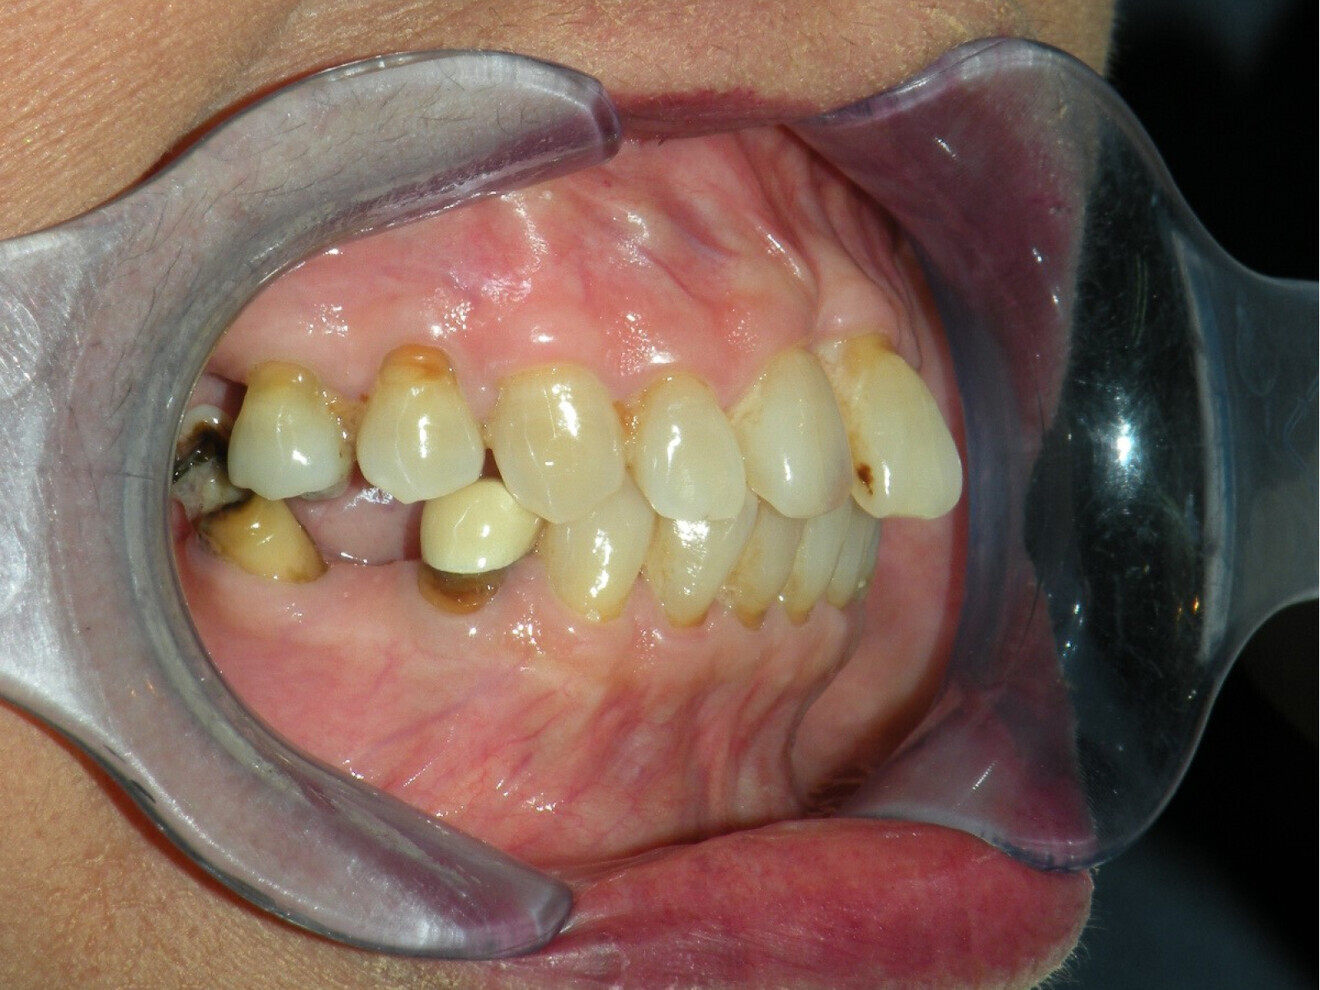

Case 2

• 50-year-old woman

• No underlying medical condition.

• Main complaint: Multiple gaps.

Intra-oral findings:

Class I malocclusion with poli diastemas in both upper and lower arch.

Overbite= 1mm Overjet = 3mm

No molar classification (absence of molars)

Class I canine on right and left side.

Upper midline (mesial to 11) on with face.

Lower midline on with the chin.